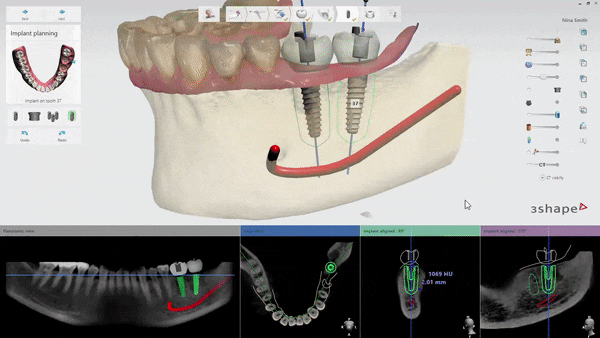

Lập kế hoạch vị trí và góc đặt implant tối ưu

Bằng cách này không chỉ vị trí hoặc góc đặt implant có thể được lên

kế hoạch trước trong quá trình phẫu thuật mô phỏng trên máy tính.

Khớp nhai implant, thiết kế mão răng

Khi thiết kế trước mão răng implant có tính đến khớp cắn.

Trên thực tế, đây là một trong những lợi thế chính.

Lên kế hoạch đặt trụ implant tránh dây thần kinh hàm dưới

Ngoài ra, vị trí chính xác của dây thần kinh

chỉ có thể được xác định bằng dữ liệu 3D.

Thông qua đó, chiều dài và góc của mô cấy có thể

được điều chỉnh để tránh chạm vào dây thần kinh trong quá trình phẫu thuật,

từ đó ngăn ngừa các tác dụng phụ như tổn thương dây thần kinh.

Sau khi xem xét tính ổn định của phẫu thuật thông qua phẫu thuật

mô phỏng trên máy tính, vị trí đặt cuối cùng sẽ được xác định.

Ảnh trên là ảnh chụp quá trình cấy ghép implant mô phỏng.

Với bức ảnh này, bạn có thể kiểm tra trước độ dày của xương

có đủ hay không khi trụ implant (vít, vật cố định) nằm bên trong xương nướu,

sau đó đặt trụ implant ở vị trí và góc chính xác hơn.

Sau khi điều chỉnh khớp cắn và độ thẳng hàng giữa răng trên và răng dưới,

hướng dẫn phẫu thuật kỹ thuật số cuối cùng được tạo ra dựa trên các chi tiết phẫu thuật đã được lên kế hoạch.